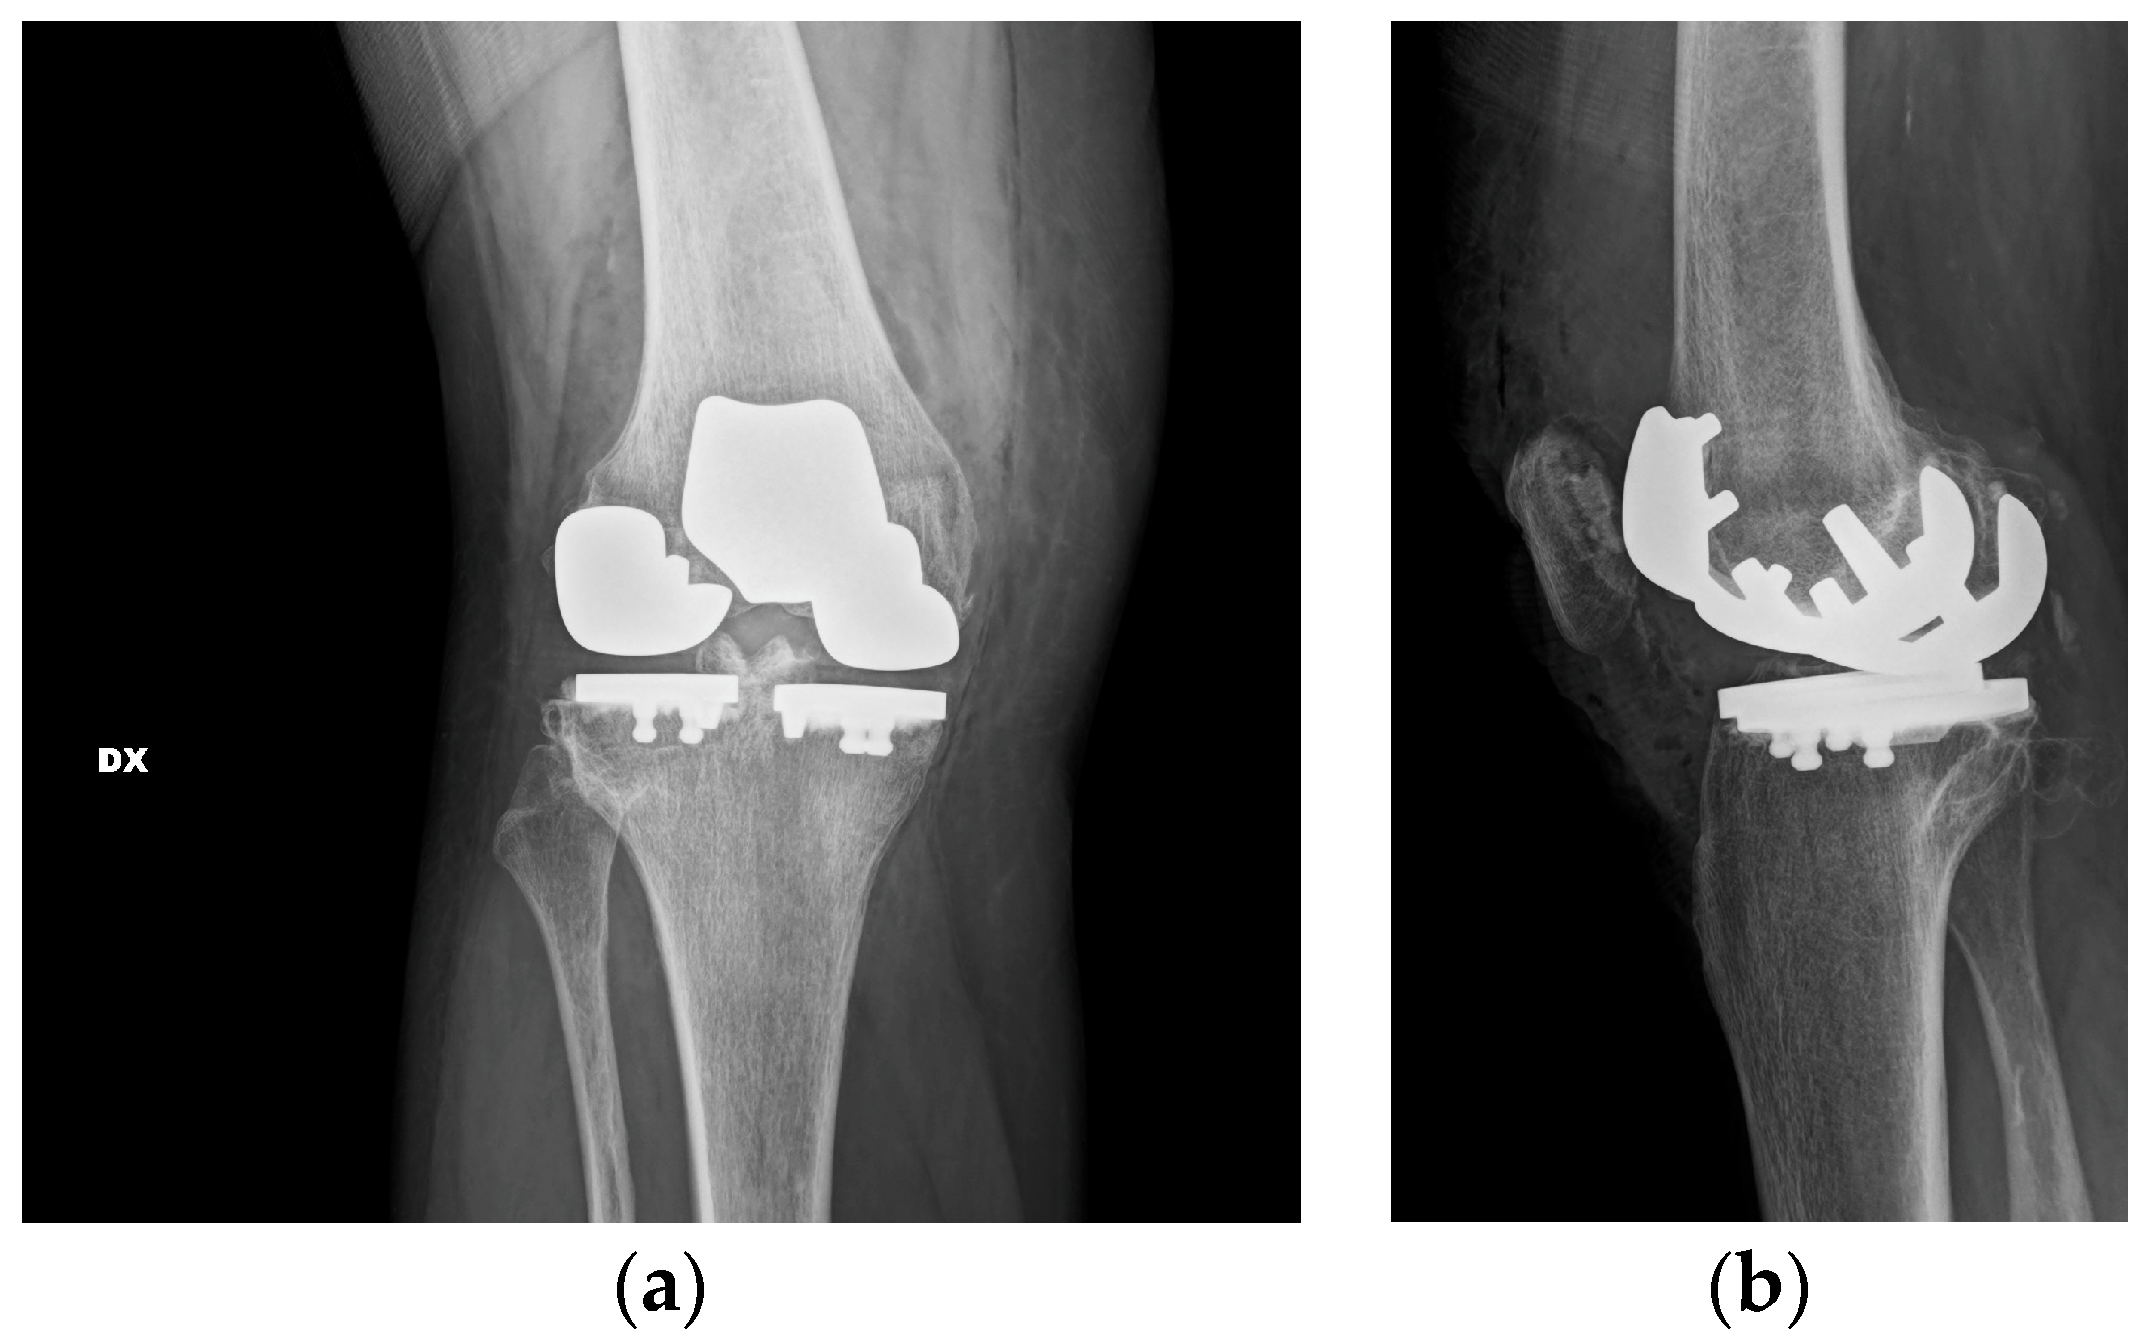

At first, the lateral tibial plateau was cemented, then the medial one, and then their bearings were added. At the end, the femoral components were cemented. The trochlear component and the patellar one were the last to be cemented (Figure 4).

Figure 4.

Component positioning. (a) Anterior view with definitive components. The two fixed bearings are on the same level to restore the correct joint line. (b) Lateral view with definitive components. Two different degrees of posterior slope for the tibial cuts.